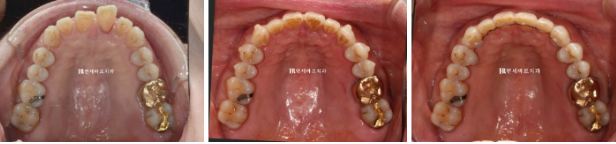

23.1~23.7

인비절라인 치료 중에는 치아에 어태치먼트가 필요합니다.

인비절라인으로 교정이 잘 안 되던 과거와 현재가 명확히 나뉘는 기준은 바로 이 어태치먼트의 유무입니다.